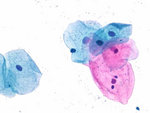

Cytocolor® Staining Kits

Cytocolor® staining kits are the optimal choice for gynecological investigations. They provide valuable information regarding the integrity, hormonal status and vaginal flora in gynecological smears. The kits are not only convenient but also rapid, allowing you to produce stains within just three minutes. In contrast to classical Papanicolaou stains, Cytocolor® requires no orange stain. Hence, both mature and keratinized cells appear pink instead of orange.

Cytocolor® staining kits are the optimal choice for gynecological investigations. They provide valuable information regarding the integrity, hormonal status and vaginal flora in gynecological smears. The kits are not only convenient but also rapid, allowing you to produce stains within just three minutes. In contrast to classical Papanicolaou stains, Cytocolor® requires no orange stain. Hence, both mature and keratinized cells appear pink instead of orange.